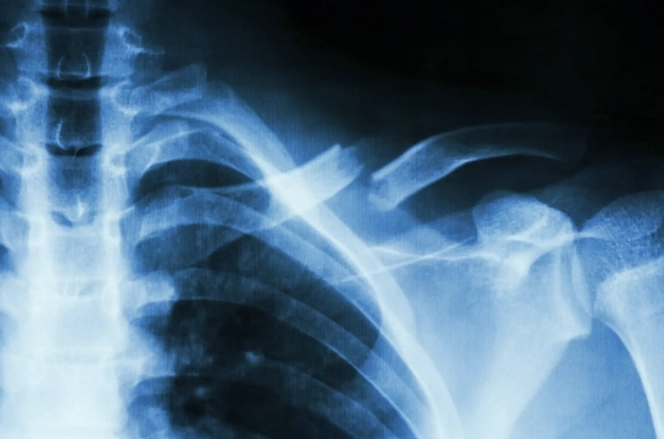

肋骨骨折後,身體會啟動自然的愈合過程,包括炎症期、修復期和重塑期。這段期間,營養攝取直接影響骨骼的再生能力。如果吃了不該吃的東西,可能會干擾這些階段,導致恢復延遲或併發症。例如,高鹽分食物會引起水腫,增加胸腔壓力,讓呼吸都變得更痛苦。而辛辣食物則可能刺激神經,加劇疼痛感。

我記得醫生告訴我,骨折愈合需要大量的蛋白質、鈣質和維生素D。這些營養素能促進骨痂形成,讓斷裂的肋骨慢慢接合。反之,如果攝取過多禁忌食物,就像在傷口上撒鹽,不僅無助恢復,還可能讓情況惡化。所以,肋骨骨折不能吃什麼,絕對不是小事,它關係到整個恢復期的舒適度和效率。

有些研究指出,飲食控制能減少併發症風險,比如肺炎或感染。肋骨骨折常伴隨呼吸困難,如果飲食不當導致腹脹或炎症,可能會讓呼吸更吃力。這點我深有體會,當初因為貪吃鹹酥雞,結果水腫搞得我連深呼吸都痛,真是自作自受。